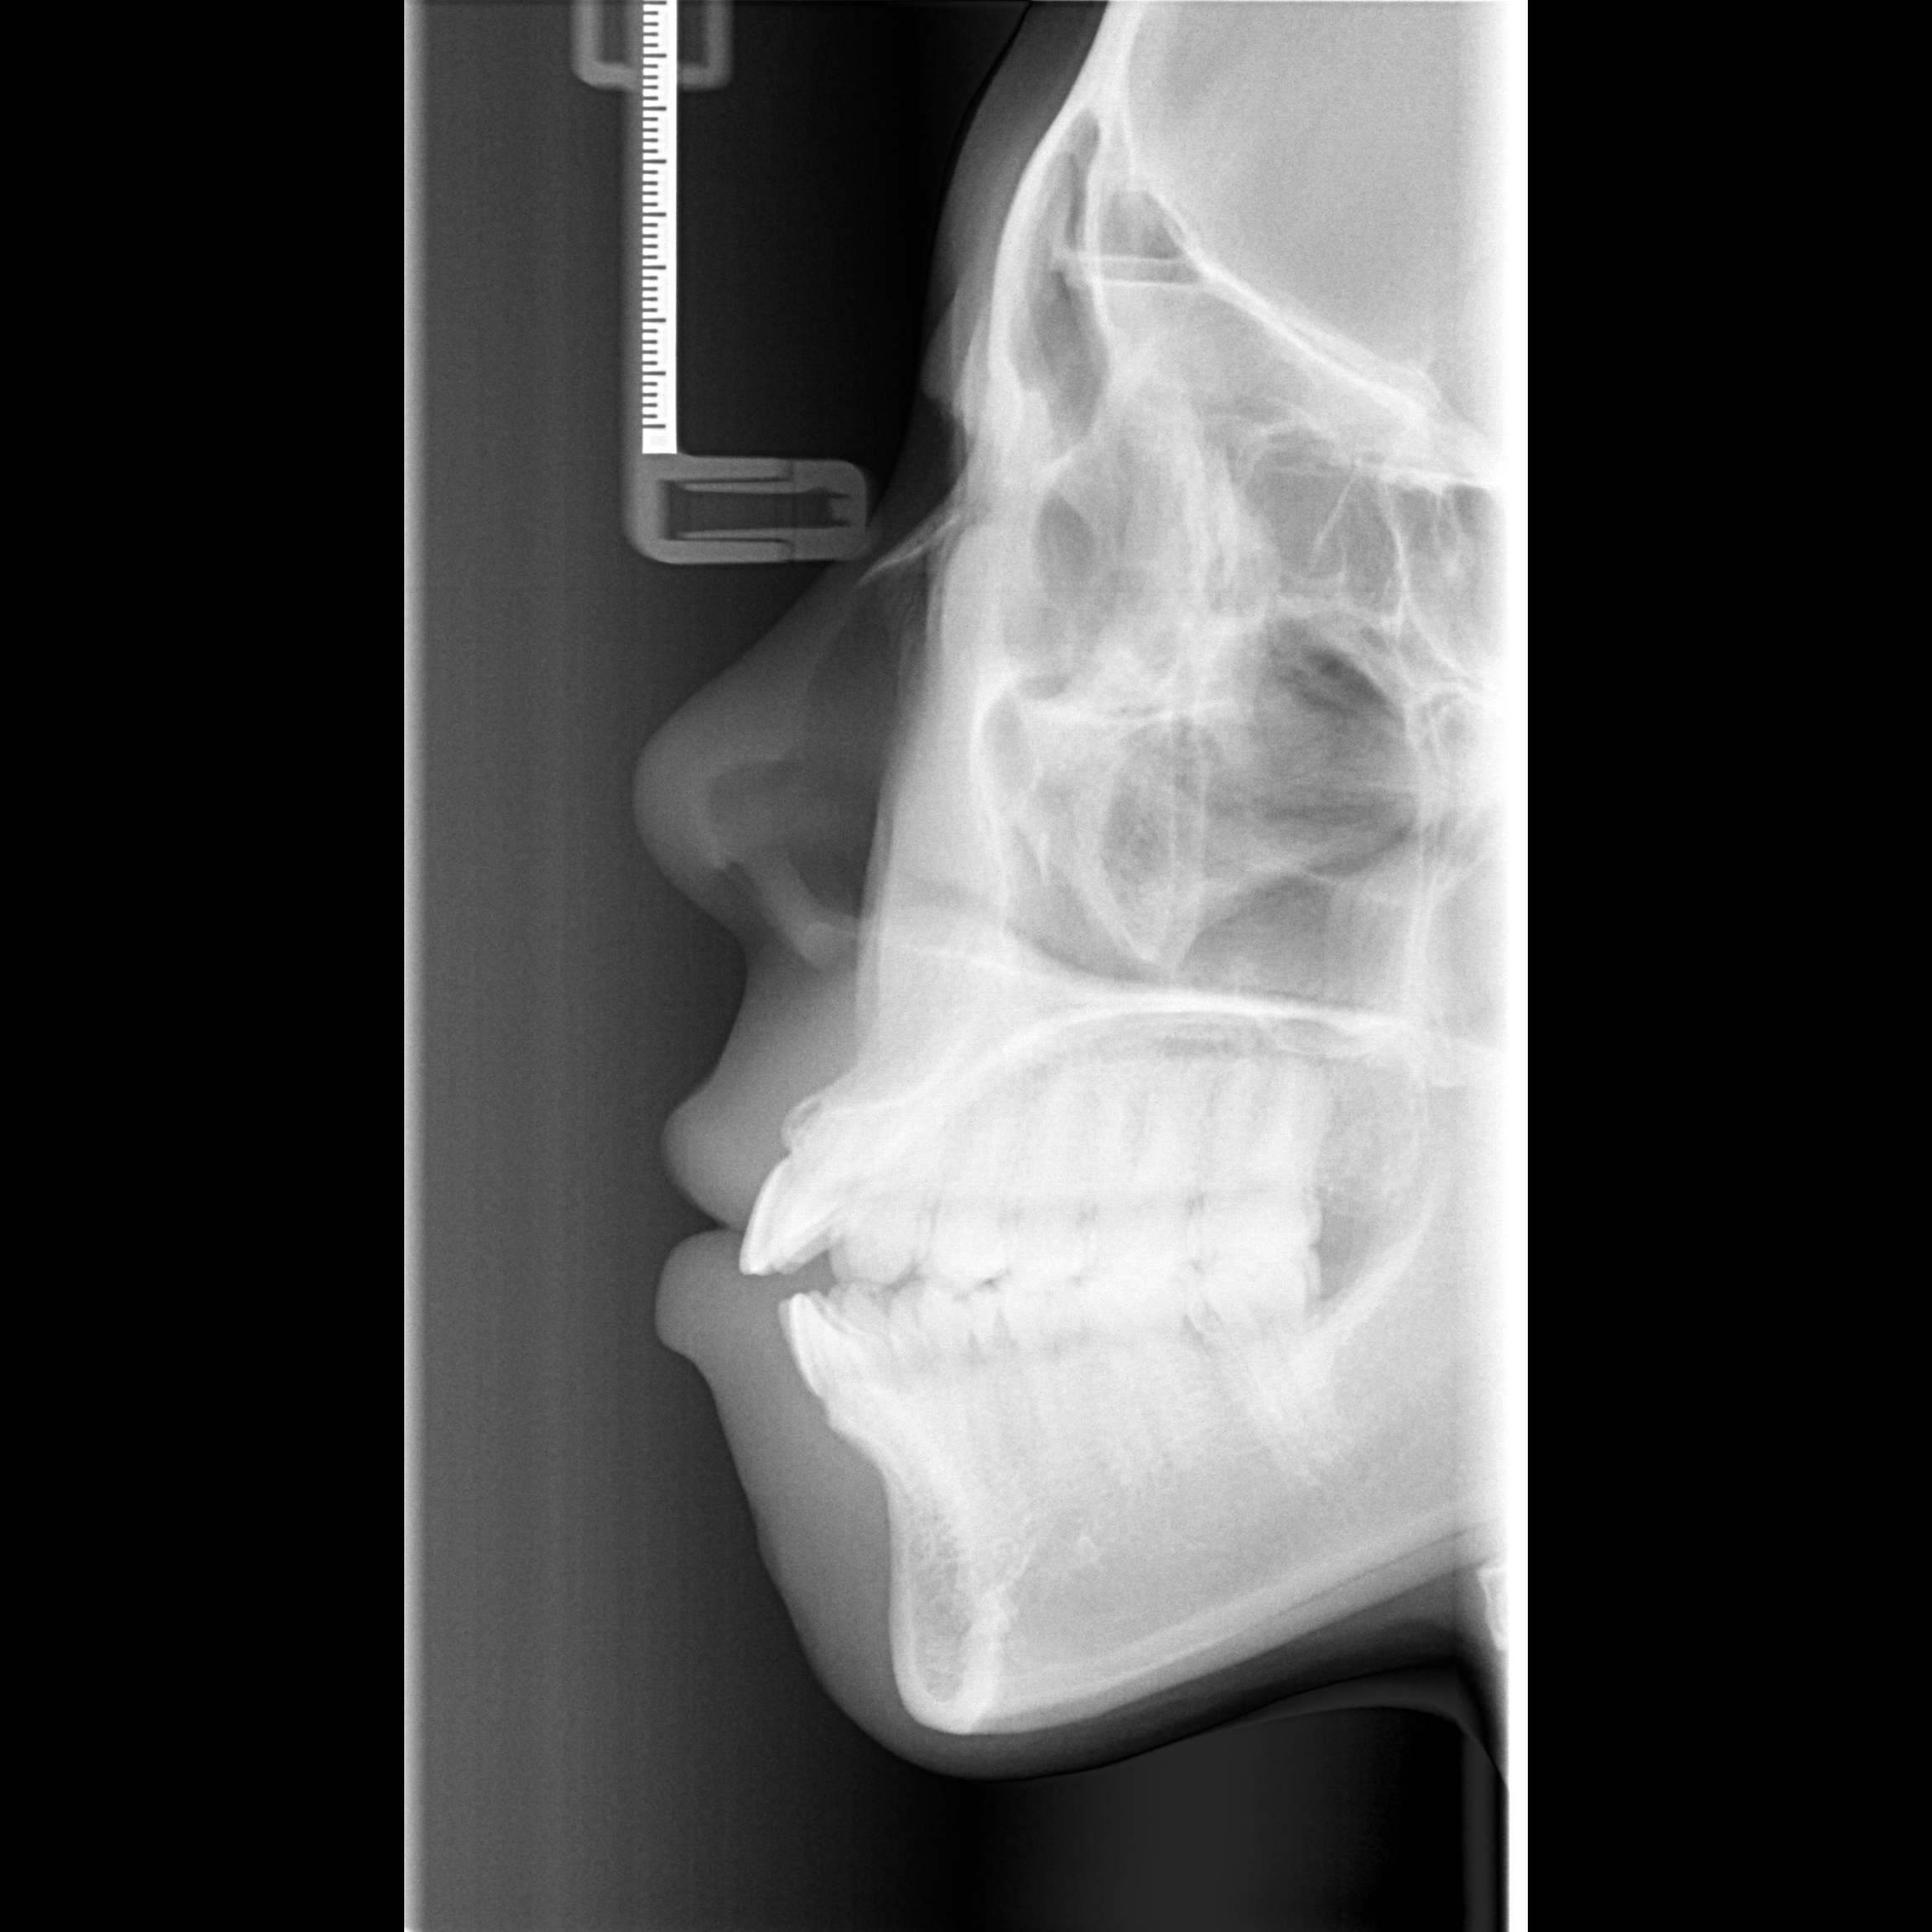

Lateral cephalogram and orthopantomogram (OPG) radiographs are routinely taken for each orthodontic patient for diagnostic and treatment planning purpose. Compared with panoramic radiograph, lateral cephalogram contains the entire craniofacial bones and soft tissue. Because of the way the lateral cephalogram were taken, the left and right craniofacial bones and teeth overlapped together, so the lateral cephalogram can provide more information than panoramic radiograph. However, no one has done any research to infer age and gender based on deep learning of lateral cephalogram.

Because the lateral cephalogram contains the cervical spine, all teeth and craniofacial bones, as well as the craniofacial soft tissue. Therefore, it can simultaneously reflect the aging changes of these areas. So far, the study of age estimation using lateral radiographs is still a blank, so we choose lateral radiographs as the research object.